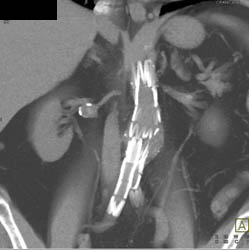

CASE NUMBER 3,554

Renal Artery Aneurysm